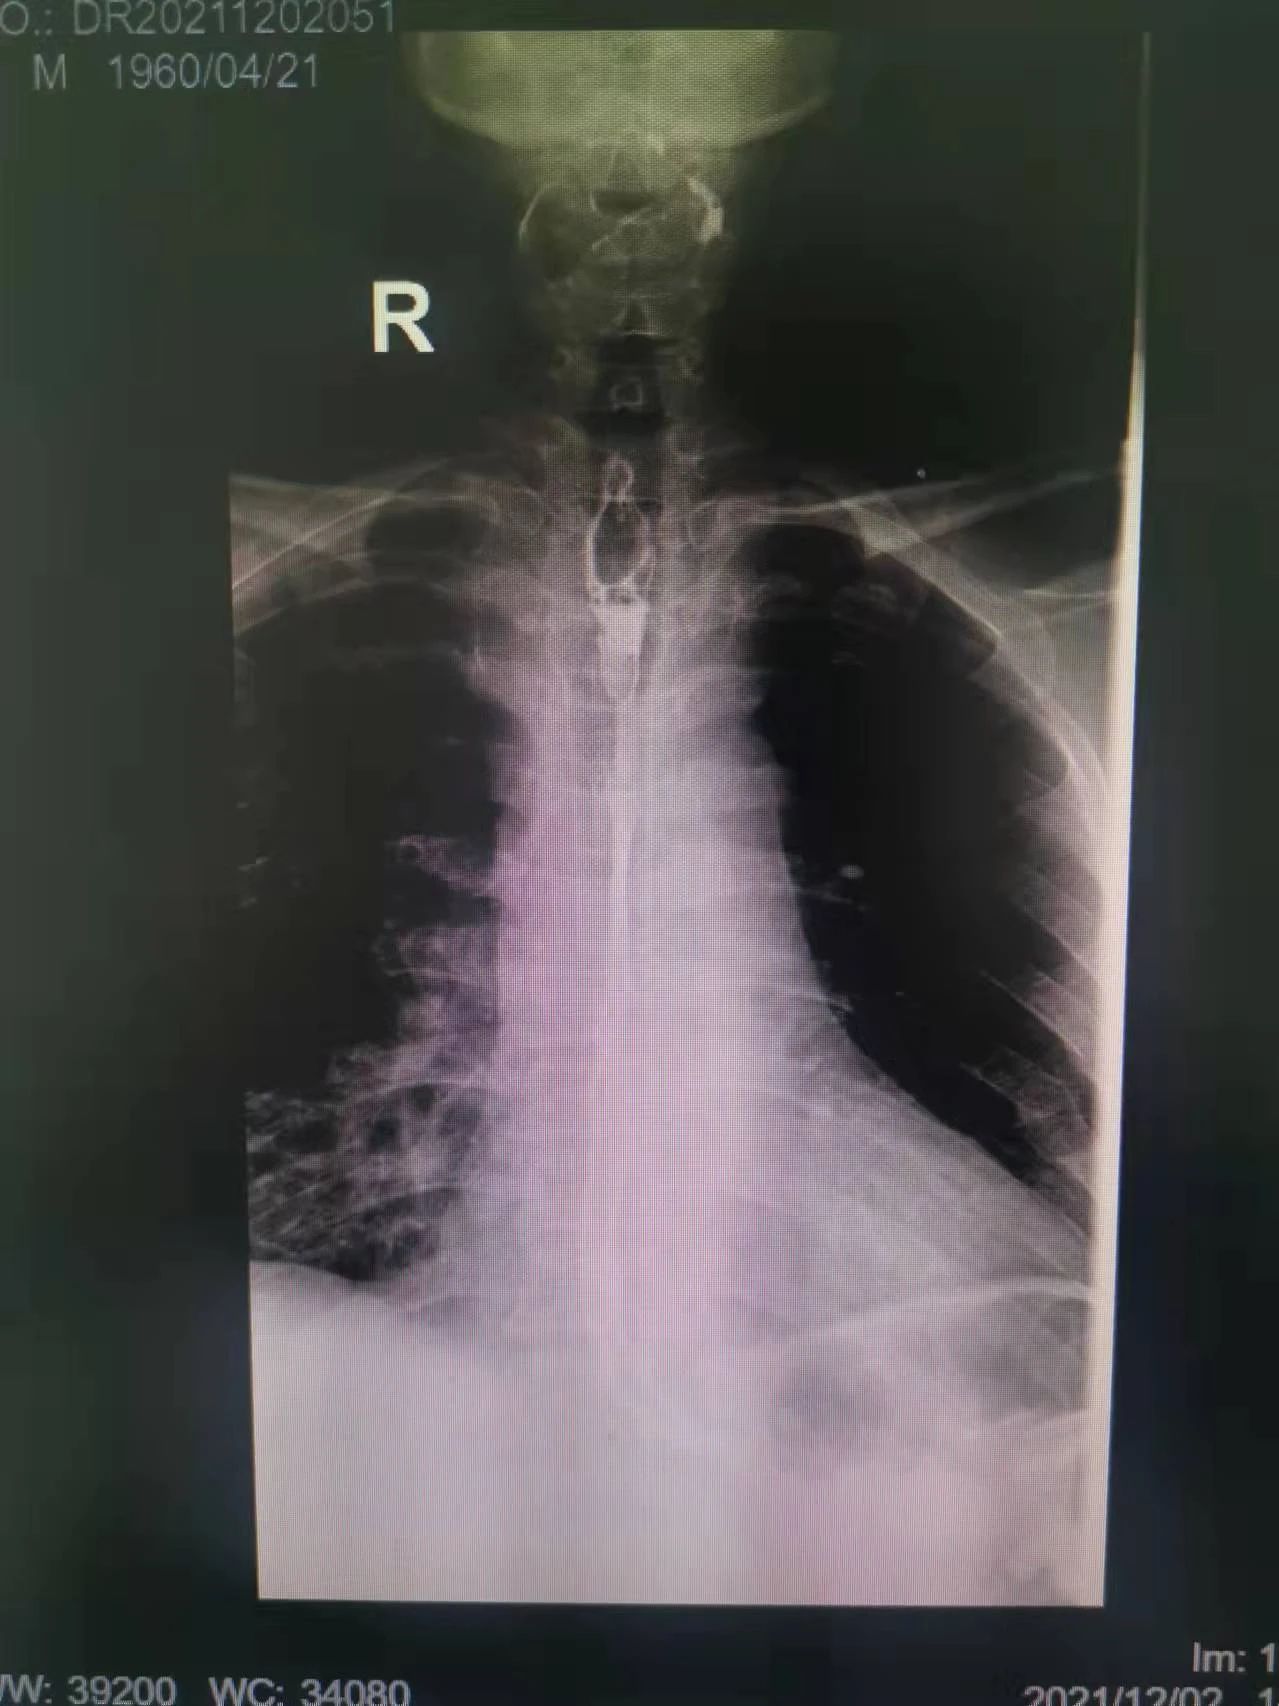

在這種情況下,我院介入二科侯主任決定通過介入治療中的食管支架植入來幫助患者實現(xiàn)這個愿望。手術當日,侯主任在機器的幫助下,將一根細細的導絲穿過腫瘤到達付大爺胃部,然后再沿著導絲,把壓縮好的支架放在腫瘤里面。通過后撤導管,把壓縮的支架打開,支架把腫瘤撐開,讓食管不再堵塞。有了支架的支撐,付大爺就可以自由地吃東西了,哪怕食管和氣管有溝通,因為支架覆蓋了腫瘤,通道堵住了,吃的東西也不會吸到肺內造成感染。這時痛痛快快地吃上一頓,也不再是奢望!

手術很順利,付大爺也在術后第2天喝到了自己日思夜想的清水,露出了久違的笑容。從某種意義上講,介入食管支架置入術的成功實施,付大爺不能進食的病已經(jīng)“治好”了,雖然從生理角度來說,付大爺可以通過終生使用腸內營養(yǎng)來維持生存,但我們所做的是致力于給予患者更好的生存體驗,或者說是尊嚴。銘記并保持一名醫(yī)者的初心,我們要做的正如那句著名的墓志銘所說:有時去治愈,常常去幫助,總是去安慰。